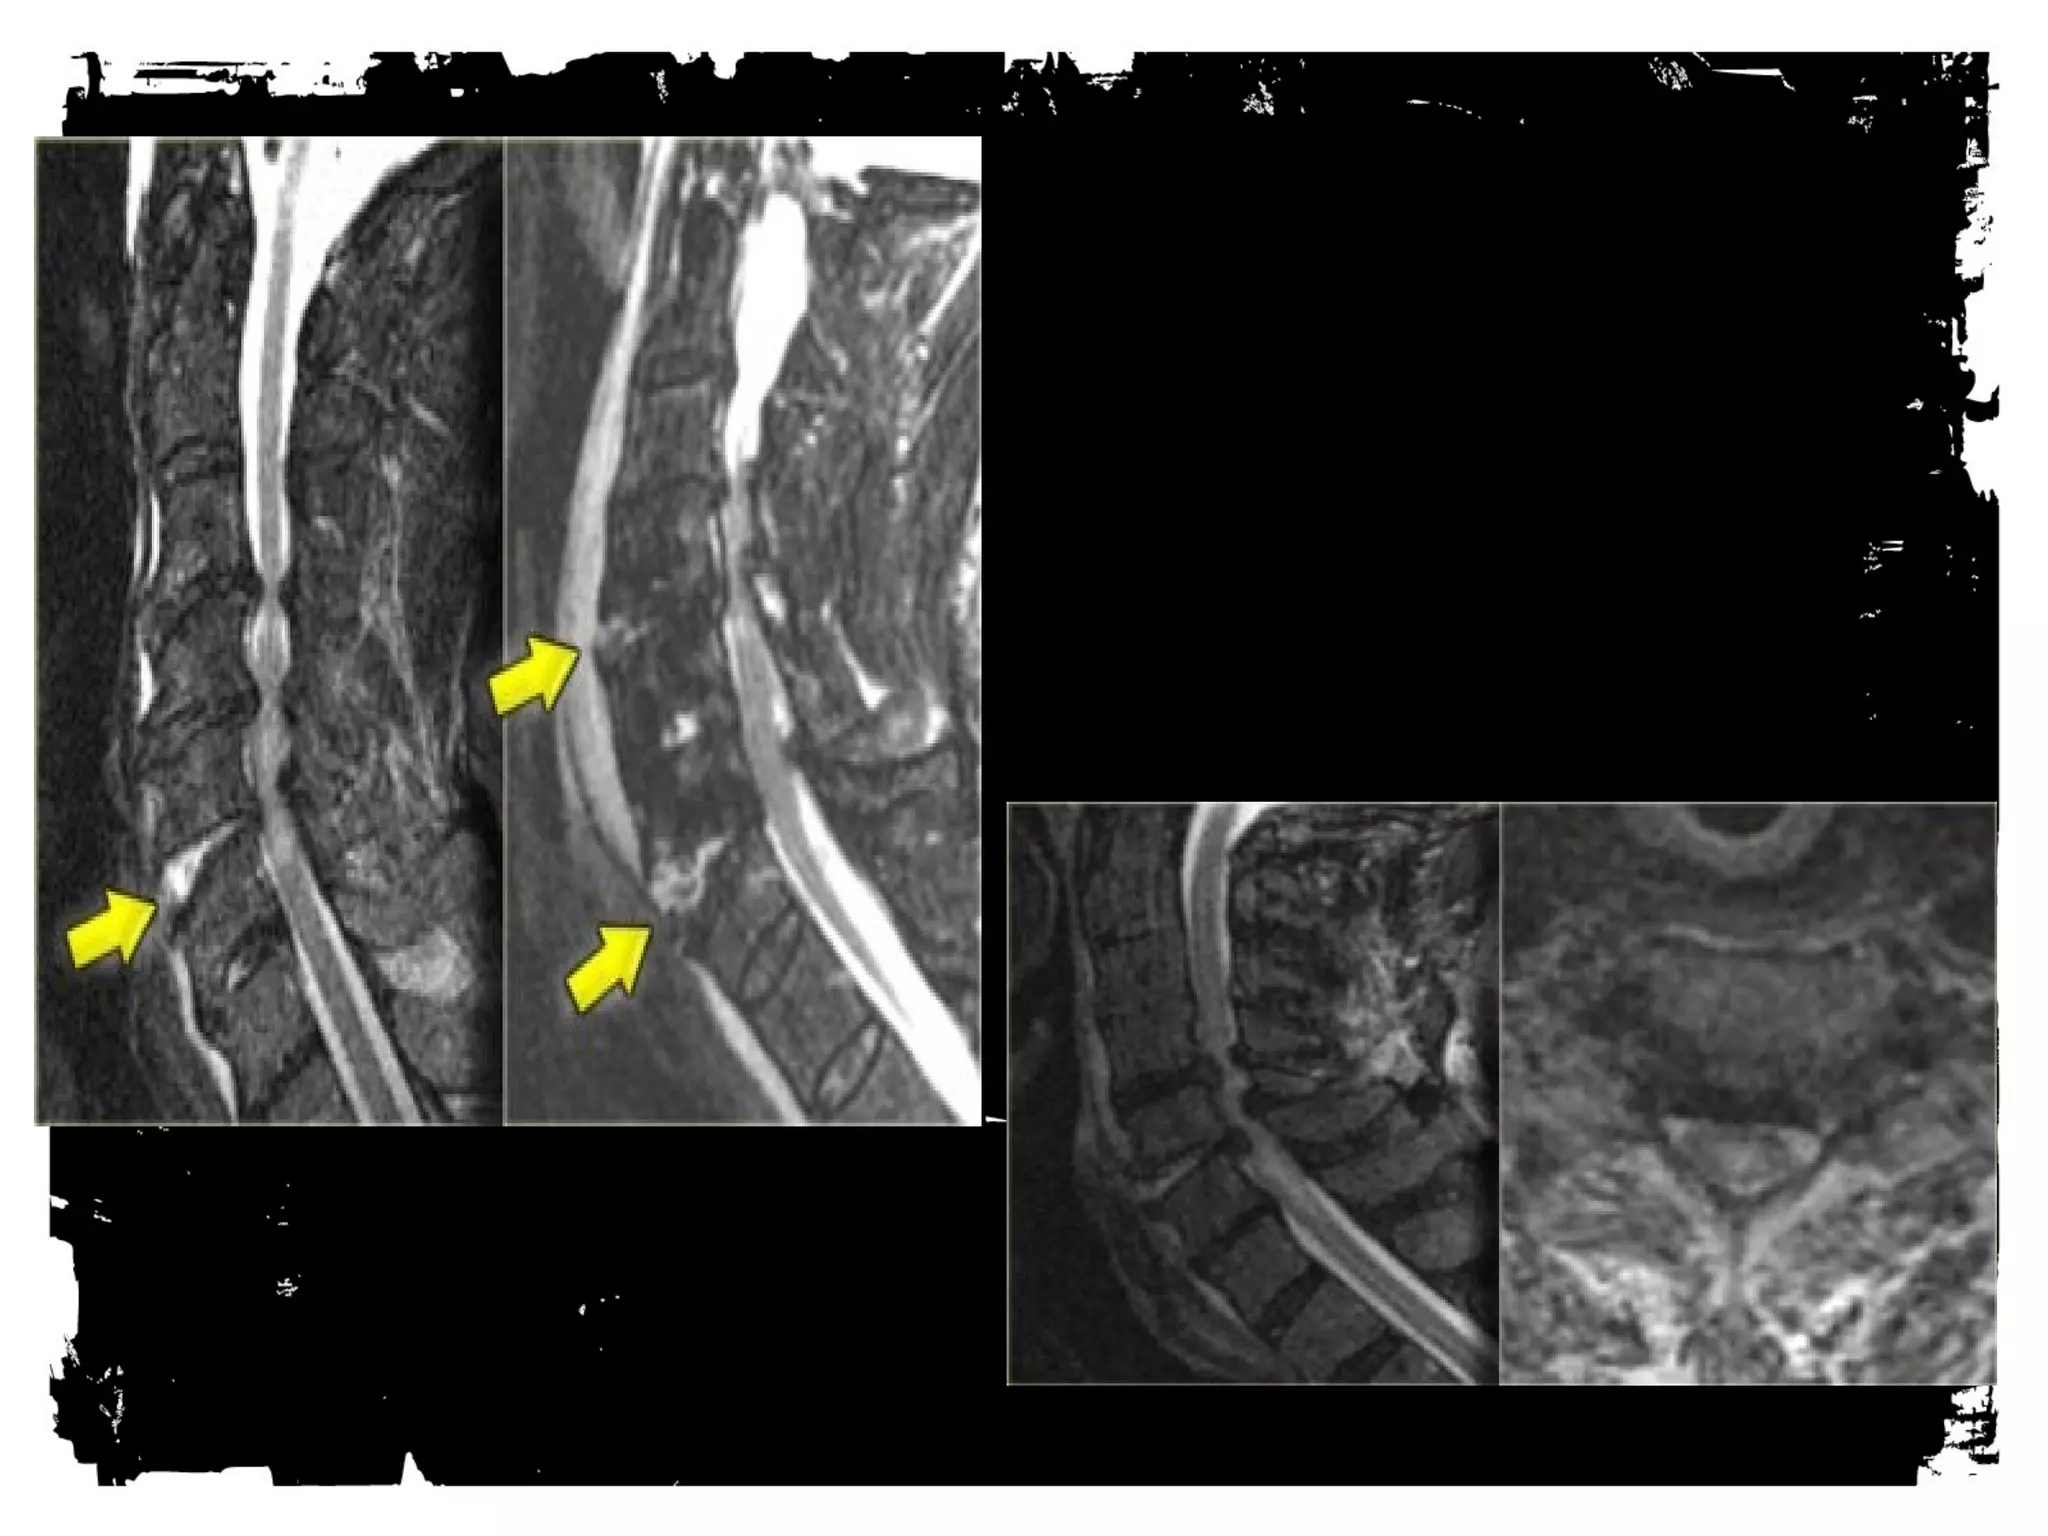

Spinal cord injury (SCI)

Spinal cord injury

There are two types of

injury to the spinal cord:

• Non-hemorrhagic with

only high signal on MR

due to edema.

• Hemorrhagic with areas of

low signal intensity within

the area of edema.

• There is a strong correlation

between the length of the

spinal cord edema and the

clinical outcome.

• The most important factor

however is whether there is

hemorrhage, since

hemorrhagic spinal cord

injury has an extremely poor

outcome.